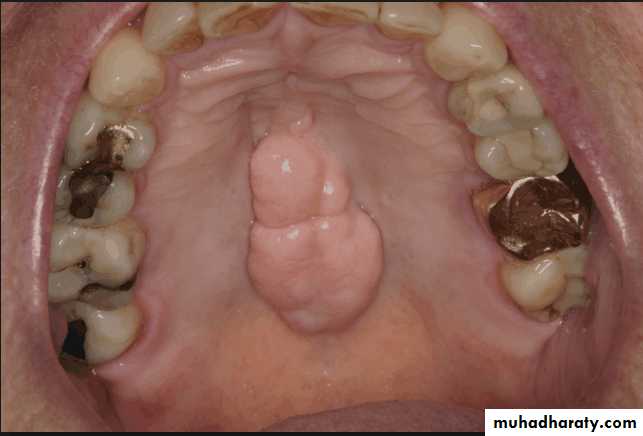

Evaluation of hard tissue abnormalities

Torus palatinus:

Removal is not necessary unless it is so large that interferes with the design and construction of the prosthesis.If removal is deemed necessary, acrylic resin surgical splint should be constructed pre operatively.

Splint is used to adapt and support the mucosal flaps in contact with the bone.

Torus mandibularis:

Usually occurs bilaterally, on the lingual surface of body of the mandible.

Tori should be removed if the patient is to wear the removable partial denture with any degree of comfort.